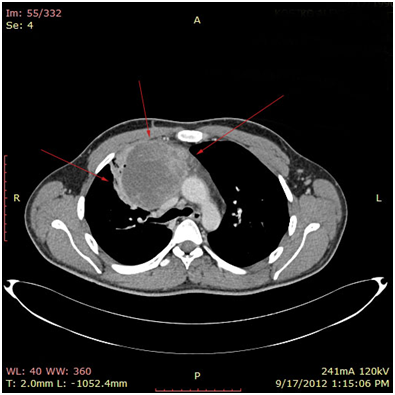

Bild 4 CT – axial plan demonstrating a 10cm Yolk sac tumor invading the truncus pulmonalis and the vena cava superior.